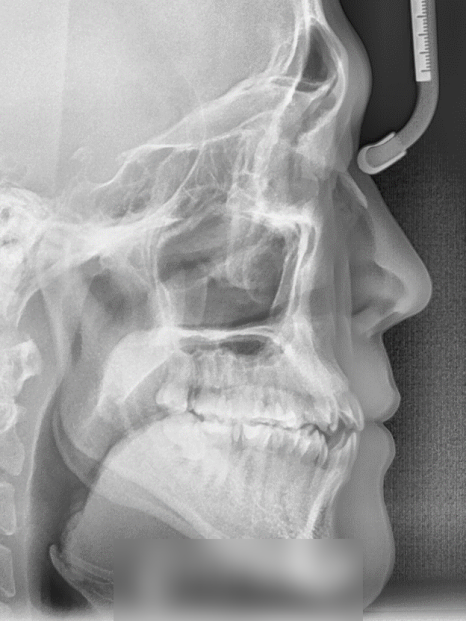

초진 사진을 확인해 본 결과

심한 총생과 반대교합 그리고

검게 썩어 있는 어금니를 볼 수 있었습니다.

절단 교합까지 함께 확인되어

이대로 내버려두었다간

턱관절이나 교합에도 좋지 않은

영향을 끼칠 거란 판단이 들었습니다.